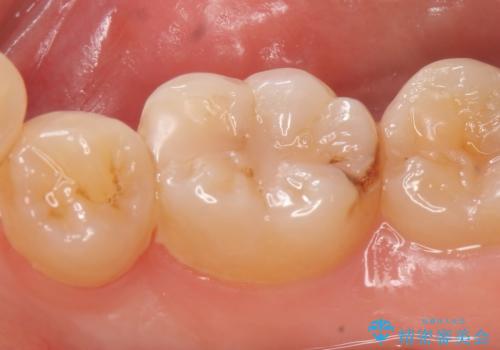

- 右下6番目の歯がしみるといらっしゃった方の症例です。

古い樹脂及び虫歯を除去後、セラミックインレーにて修復を行いました。